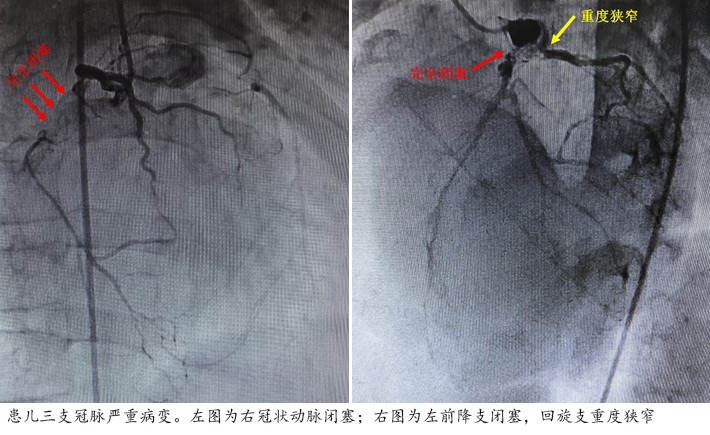

东方网记者刘轶琳8月23日报道:近日,国家儿童医学中心复旦大学附属儿科医院成功完成国内首例川崎病合并冠状动脉病变患儿冠状动脉搭桥术后吻合口再狭窄支架植入术,患儿术后恢复良好。 小伦自2岁起便与川崎病及其引发的严重冠状动脉病变相伴,几经生死考验。2021年,在复旦儿科,心内科刘芳教授团队进行了细致的评估和冠状动脉造影手术,揭示了令人心惊的现实——左冠状动脉前降支和右冠状动脉完全闭塞,仅存的回旋支也存在狭窄病变(见下图),小伦的生命仿佛悬于一线。